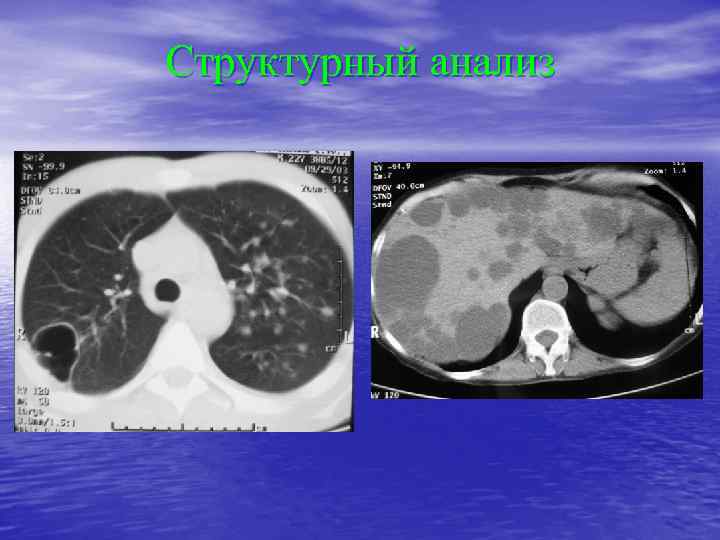

Структурный анализ Оценка основных макроскопических признаков: - положение - форма - размеры - характер контуров и структур патологически измененных участков

Структурный анализ